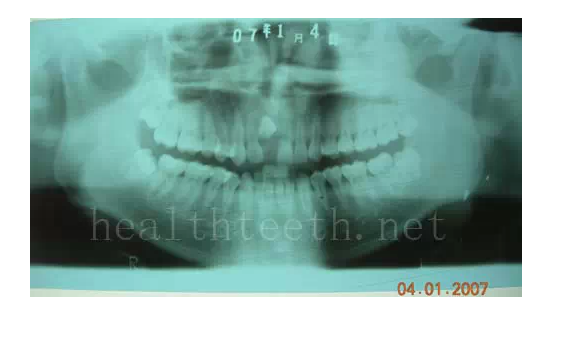

3、多生牙

病例1

病例2